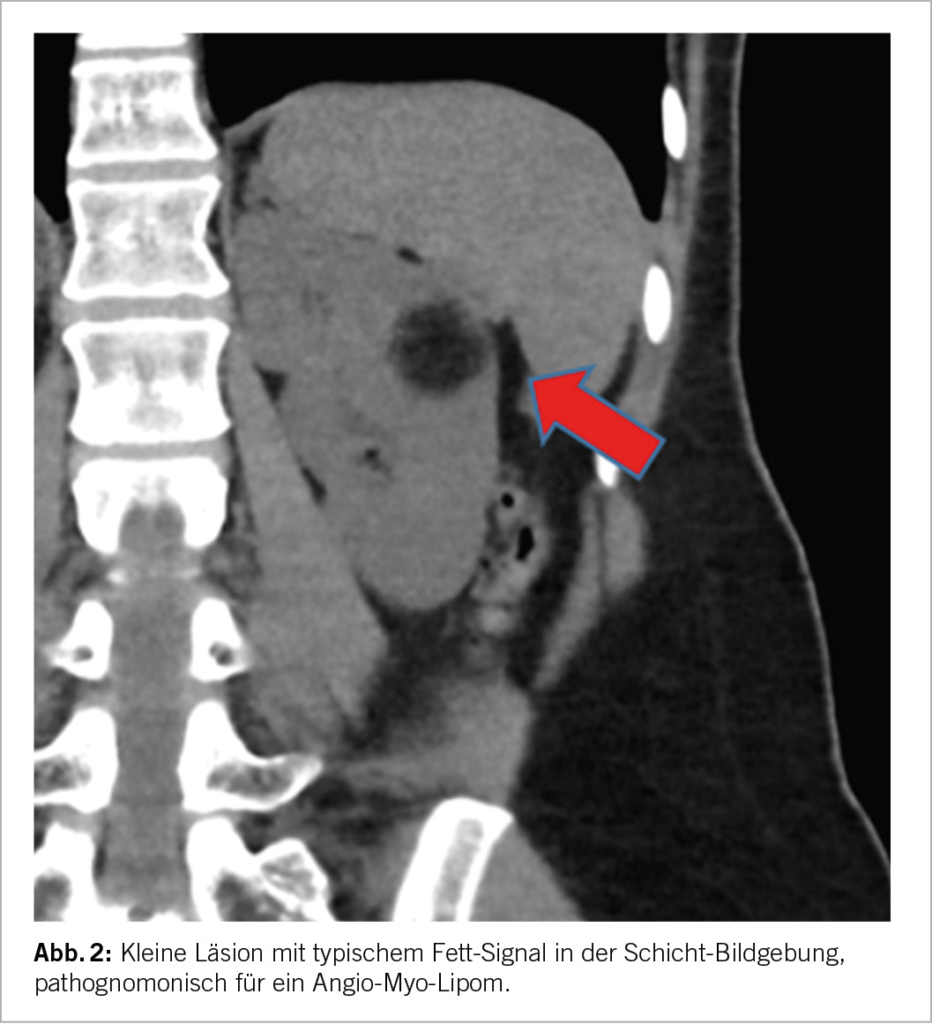

Die bildgebende Grundlage für die Beurteilung einer SRM ist entweder eine qualitativ hochwertige CT oder MRI-Untersuchung nativ sowie mit Kontrastmittel. Beide Verfahren haben gewisse Vor- und Nachteile, eine eindeutige Überlegenheit der einen gegenüber der anderen gibt es nicht (9). Die wichtigen Aspekte hier sind i) der allfällige Nachweis von Fettgewebe, welcher richtungsweisend für ein Angio-Myolipom und somit eine gutartige Läsion wäre, ii) das Kontrastmittelverhalten, wobei eine deutliche Anreicherung eine Malignität wahrscheinlicher macht, iii) die Charakterisierung allfälliger zystischer Läsionen basierend auf der Bosniak-Klassifikation (10) sowie iv) die Beschreibung der Tumor-Komplexität, z.B. unter Verwendung der RENAL Scores. Aus letzterer Information lässt sich insbesondere auch eine Einschätzung der Komplexität einer allfälligen chirurgischen Intervention abschätzen. Tumoren <3cm zeigen verglichen mit SRM von 3-4cm ein noch geringeres Risiko für Malignität oder aggressives biologisches Verhalten (6, 11). Liegen bereits mehrere Bilder vor und erlauben somit eine Aussage über die Dynamik, so ist ein rasches Wachstum (>5mm pro Jahr) ebenfalls ein Zeichen für Malignität und aggressives Verhalten. Als letzter Aspekt und somit v) sollte die Klinik berücksichtigt werden, bei Fieber und Infekt-Zeichen kommt differentialdiagnostisch eine entzündliche Genese (Abszess/Pyelonephritis) in Betracht. Ansonsten gibt es aber keine weiteren bildmorphologischen Aspekte, welche eine verlässliche Aussage in Hinblick auf die reale biologische Aggressivität der SRM ableiten liessen.